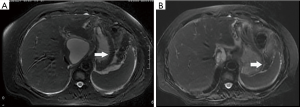

Among the AP patients, wall thickening involved duodenum (Figure 1) (27%), ascending colon (26%), stomach (20%), transverse colon (15%), jejunum (Figure 2) (14%) and ileum (6%). Dilatation of the gastrointestinal tract was seen in 8% (Figure 2, Table 2).

During treatment, 62 patients had follow up MRI examination, 16 of whom (26%) had a gastrointestinal tract abnormality on follow up examination, significantly lower than that on the initial MRI (P<0.05) (Figures 3-7). The frequencies of gastrointestinal tract abnormalities for initial and follow-up MRI examination are shown in Table 3. The difference for the frequencies of stomach, duodenum, jejunum, ileum, ascending and descending abnormal changes between before and after the treatment had statistical significance (P<0.05). There was no difference of transverse colon and bowel dilatation before and after the treatment (P≥0.05).

In the follow-up MRI exam, the structure of gastrointestinal tract restored to revert in MRI, coinciding with relief of abdominal pain, recovered appetite, cessation of hematuria, amylase recovery and anal passing gas.

In this study gastrointestinal tract wall thickening was the most common finding in AP patients. Inflammatory substances can stimulate the gastrointestinal tract in patients with AP, leading to the excessive output of gastric juices and subsequent mucosal and submucosal edema (27). Some patients exhibit a three-layer structure referred to as the “target sign” (28). Tolan et al. (29) considered this pattern acute wall edema, and noted a direct correlation with inflammatory activity. In this study we found most AP patients exhibited gastrointestinal tract wall thickening, some with a stratified appearance on MRI that was similar to the “target sign” (28). After treatment, the mural stratification resolved on follow-up MRI. Our results suggested that the thickened intestinal wall in AP patients is derived from acute wall edema and can resolve soon after treatment.